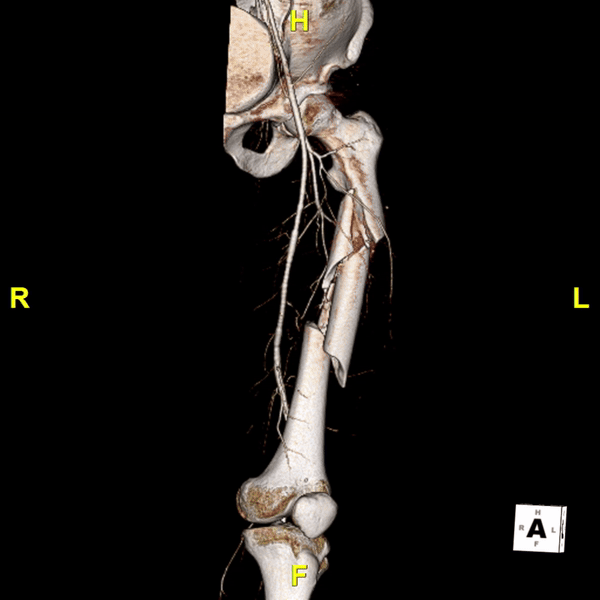

Figure E: A 3D reconstruction of the femur shows a severely comminuted fracture of the left femoral shaft with significant shortening, and nearby vascular structures.